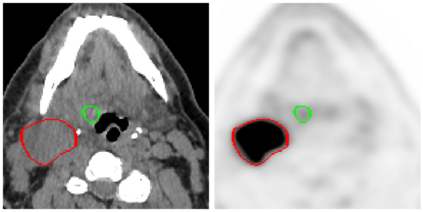

This paper presents an overview of the second edition of the HEad and neCK TumOR (HECKTOR) challenge, organized as a satellite event of the 24th International Conference on Medical Image Computing and Computer Assisted Intervention (MICCAI) 2021. The challenge is composed of three tasks related to the automatic analysis of PET/CT images for patients with Head and Neck cancer (H&N), focusing on the oropharynx region. Task 1 is the automatic segmentation of H&N primary Gross Tumor Volume (GTVt) in FDG-PET/CT images. Task 2 is the automatic prediction of Progression Free Survival (PFS) from the same FDG-PET/CT. Finally, Task 3 is the same as Task 2 with ground truth GTVt annotations provided to the participants. The data were collected from six centers for a total of 325 images, split into 224 training and 101 testing cases. The interest in the challenge was highlighted by the important participation with 103 registered teams and 448 result submissions. The best methods obtained a Dice Similarity Coefficient (DSC) of 0.7591 in the first task, and a Concordance index (C-index) of 0.7196 and 0.6978 in Tasks 2 and 3, respectively. In all tasks, simplicity of the approach was found to be key to ensure generalization performance. The comparison of the PFS prediction performance in Tasks 2 and 3 suggests that providing the GTVt contour was not crucial to achieve best results, which indicates that fully automatic methods can be used. This potentially obviates the need for GTVt contouring, opening avenues for reproducible and large scale radiomics studies including thousands potential subjects.